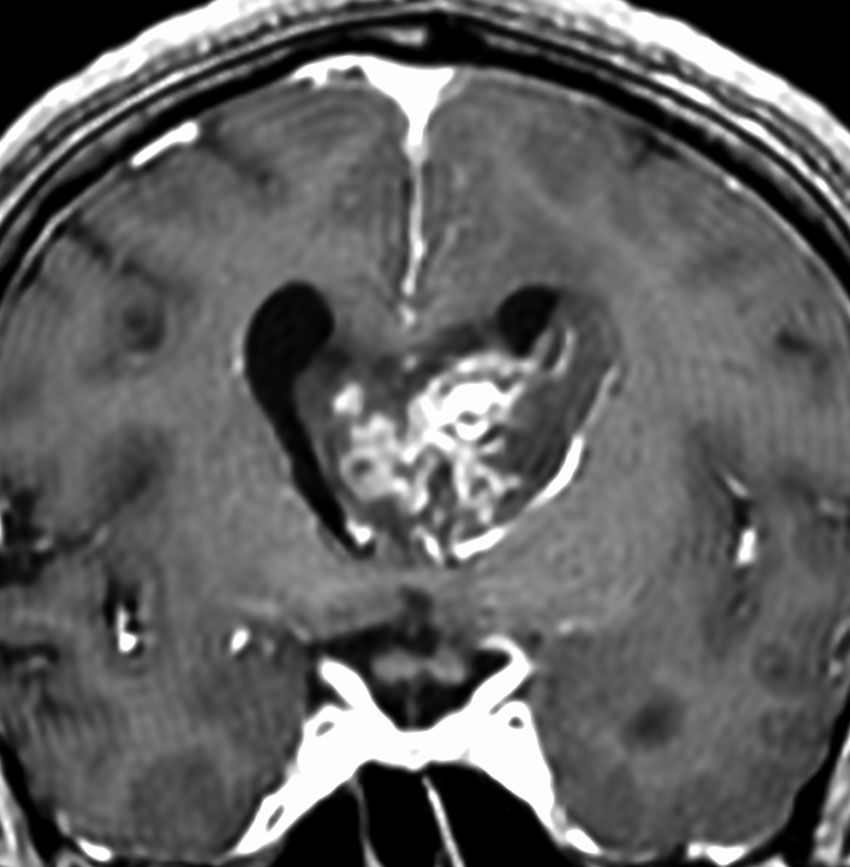

左尾状核から発生したものです。モンロー孔を閉塞して,片側性水頭症となっています。腫瘍がトリュフみたいにゴツゴツしているのも特徴です。

下のガドリニウム増強T1では,部分的に増強されます。

もちろん無症状ですが,年齢が若かったので全摘出しました。